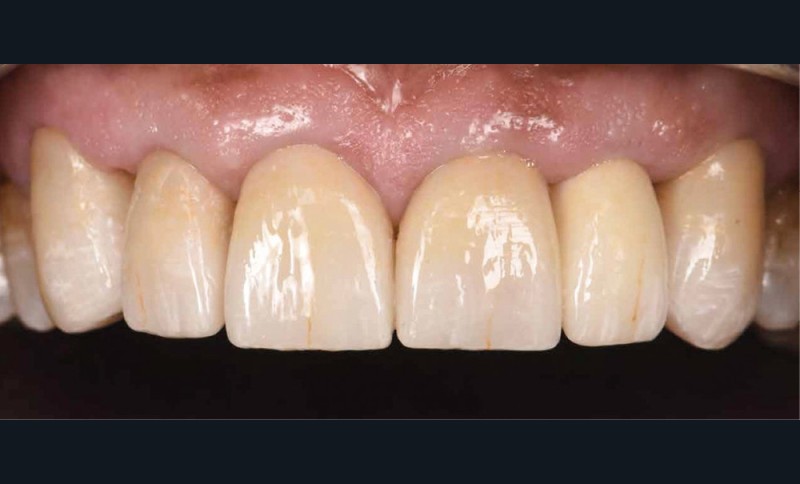

Le prothésiste réalise six RACCs en vitrocéramique renforcée au disilicate de lithium en technique pressée. Des caractérisations sont présentes pour mimer l’usure physiologique (fig. 5). Une chape « Haute Opacité » (HO) permettra de masquer l’effet grisâtre de l’inlay-core (fig. 6).

La troisième et dernière étape consiste en la réalisation du collage des RACCs via un protocole de collage strict, précédée par la vérification de l’ajustage des pièces (fig. 7) : l’isolation est primordiale via l’utilisation d’un champ opératoire médium, de ligatures et bandes en téflon (fig. 8 et 9) ainsi que de crampons B4 (fig. 10) pour exposer les limites de préparations. La validation de l’occlusion statique et dynamique est réalisée, suivie par un polissage soigneux des limites (fig. 11).

Le rapport de ce cas clinique permet d’illustrer certaines techniques modernes (planification esthétique informatisée, mock up) qui, couplées au progrès des matériaux et des techniques de collage, assurent un bon pronostic aux restaurations. La communication est au centre de nos thérapeutiques : que ce soit entre le praticien et le patient ou entre le praticien et le prothésiste. Ces derniers sont de véritables artistes céramistes à qui il faut donner tous les outils nécessaires. Nous devons également raisonner nos patients. « Envisager l’équilibre harmonieux comme la somme de déséquilibres. »